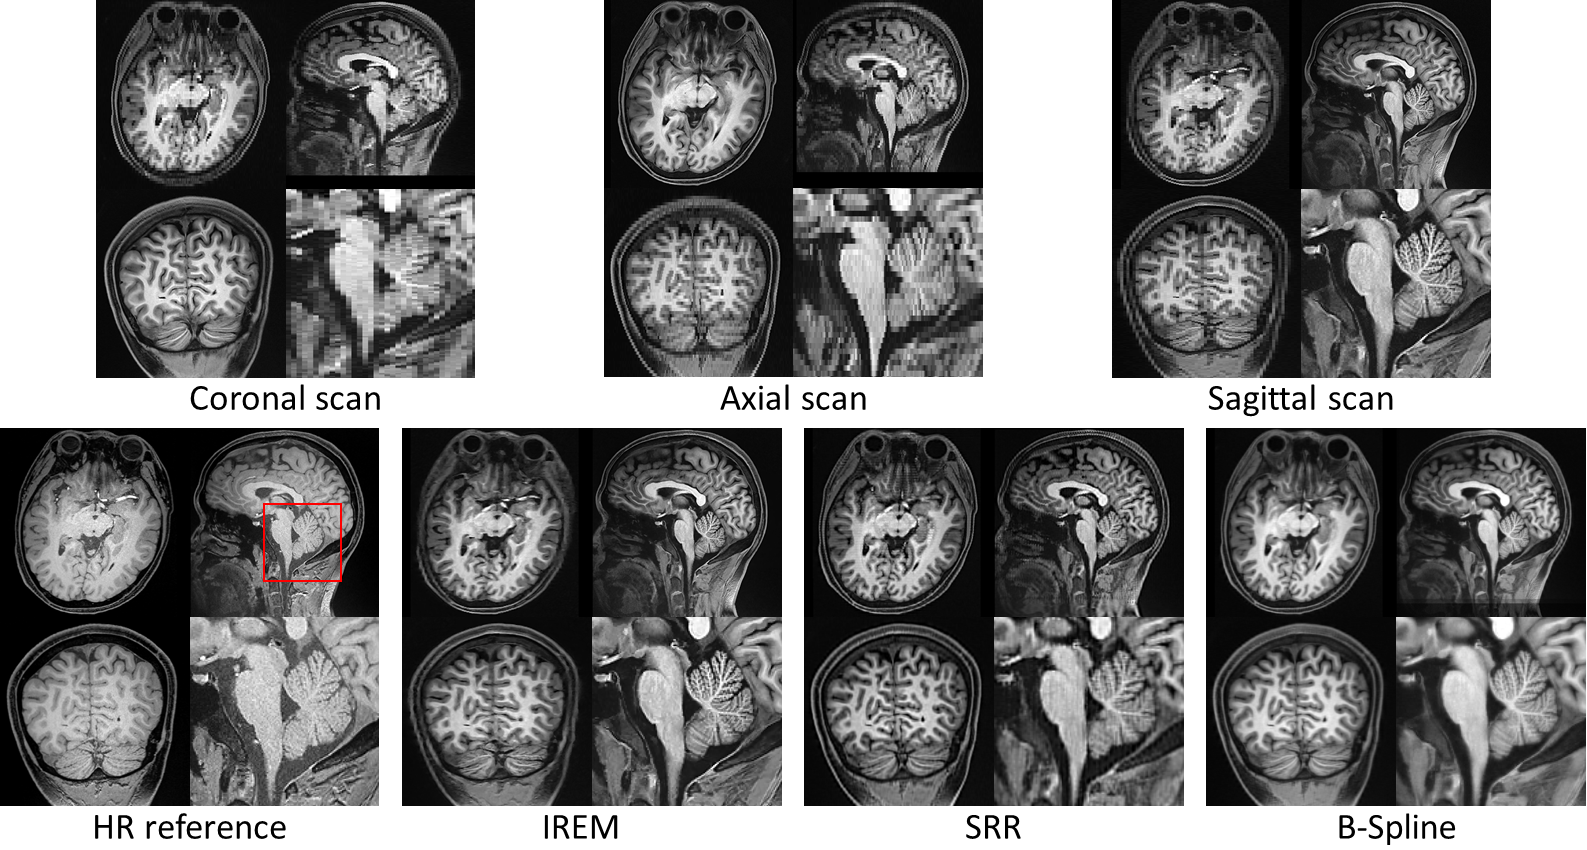

基于真实采集环境中的实验结果(如图1所示)可以看出,相对于SRR和B样条插值重建方法,该方法获得了更清晰的无伪影重建图像。此外,相比直接采集的真实高清高分辨率图像,该方法的重建结果在达到了同等图像细节的同时,提高了图像新信噪比。因此相较于直接扫描成像高清高分辨率图像,该重建方法是一种更有效的方式。

图1. 基于真实采集数据的实验结果。从上到下,从左到右分别为:基于冠状面(Coronal plane)、横断面(Axial plane)、矢状面(Sagittal plane)采集的非各向同性的低清图像;真实的高清高分辨率参考图像;该工作提出的IREM方法的重建结果;SRR方法重建结果;B样条插值重建结果。